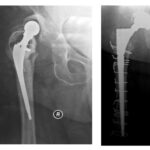

Στην εικόνα 1 επάνω αριστερά, ασθενής με φθορά στο “πλαστικό” της αρθροπλαστικής, χωρίς σημαντικά συμπτώματα. Συστήσαμε άμεση επέμβαση αντικατάστασης, συμβουλή που δεν ακολούθησε. Λίγους μήνες μετά, κάτω αριστερά, η πρόθεση της κοτύλης μετακινήθηκε εμφανώς πλέον και η αρθροπλαστική εξαρθρώθηκε. Αντιμετωπίστηκε (δεξιά) με επέμβαση αναθεώρησης της κοτύλης με τοποθέτηση οστικού μοσχεύματος και ειδικού  τύπου πρόθεση, με άριστο αποτέλεσμα.